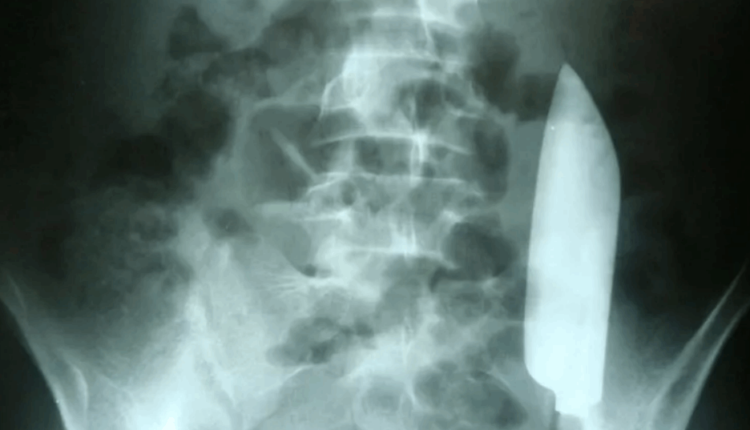

ذهب رجل يعاني من آلام في المعدة إلى المستشفى ليكتشف أن نصل سكين طوله 6 بوصات داخل بطنه.

وتعرض الرجل، وفق ما نقل موقع “نيوزويك”، وهو شاب من نيبال يبلغ من العمر 22 عامًا، للطعن في شجار في اليوم السابق، حيث قام أحد العاملين في مجال الرعاية الصحية في متجر طبي محلي بخياطة الجرح، لكنه لم يتحقق مما إذا كان النصل لا يزال بداخله، لأنه لم يكن هناك دليل مرئي على أن هذا هو الحال.

وفي اليوم التالي، ذهب الرجل إلى المستشفى وهو يعاني من “ألم خفيف مستمر في الجانب الأيسر من أسفل البطن”، دون أي علامات للغثيان أو القيء أو الإسهال أو الإمساك.

وبعد التقاط الأشعة السينية، وجد الأطباء أن النصل الضخم كان لا يزال بالداخل بالفعل، وكان يطفو على بطنه من جانبه الأيمن إلى يساره، دون إصابته بأضرار على ما يبدو بأي أعضاء داخلية أخرى، وفقًا لتقرير حالة نُشر في مجلة Cureus.